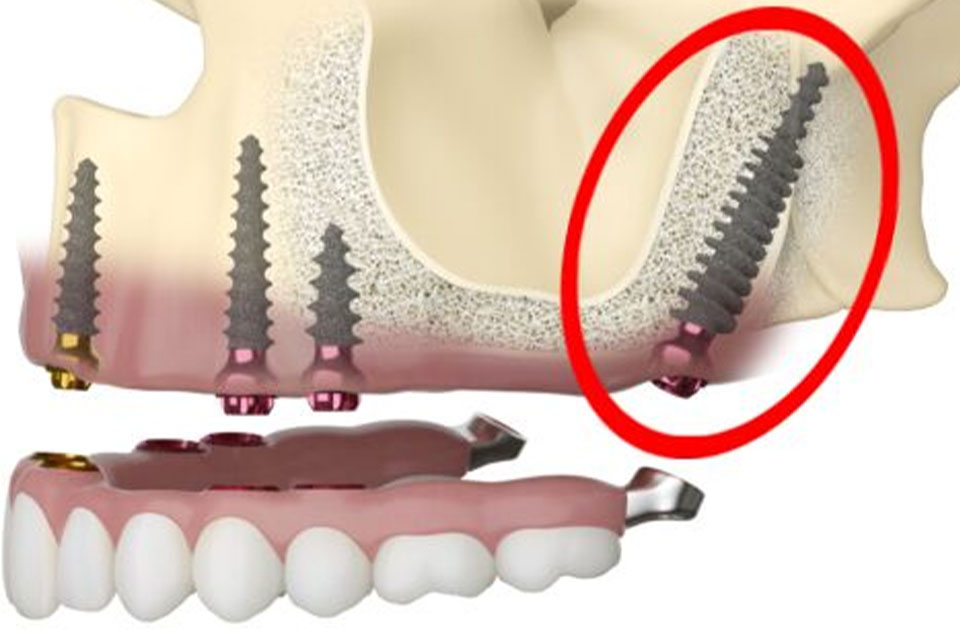

این نوع ایمپلنت به ویژه برای بیمارانی که دچار کمبود استخوان در فک هستند، طراحی شده و به استخوان زیگوماتیک (استخوان گونه) متصل میشود.

- عمل جراحی: ایجاد برش در لثه و قرار دادن ایمپلنت در استخوان زیگوماتیک. این مرحله نیازمند دقت و مهارت بالای جراح است.

این نوع ایمپلنت به ویژه برای بیمارانی که استخوان فک کافی ندارند، یک گزینه قابل اعتماد به شمار میآید. با استفاده از استخوان زیگوماتیک، این نوع ایمپلنت میتواند به خوبی در دهان قرار گیرد و عملکرد بهتری ارائه دهد.

کاهش نیاز به پیوند استخوان

در بسیاری از موارد، بیماران به پیوند استخوان نیاز ندارند، زیرا ایمپلنت زیگوماتیک به استخوان زیگوماتیک متصل میشود. این امر نه تنها هزینههای درمان را کاهش میدهد بلکه زمان بهبودی را نیز کوتاهتر میکند.